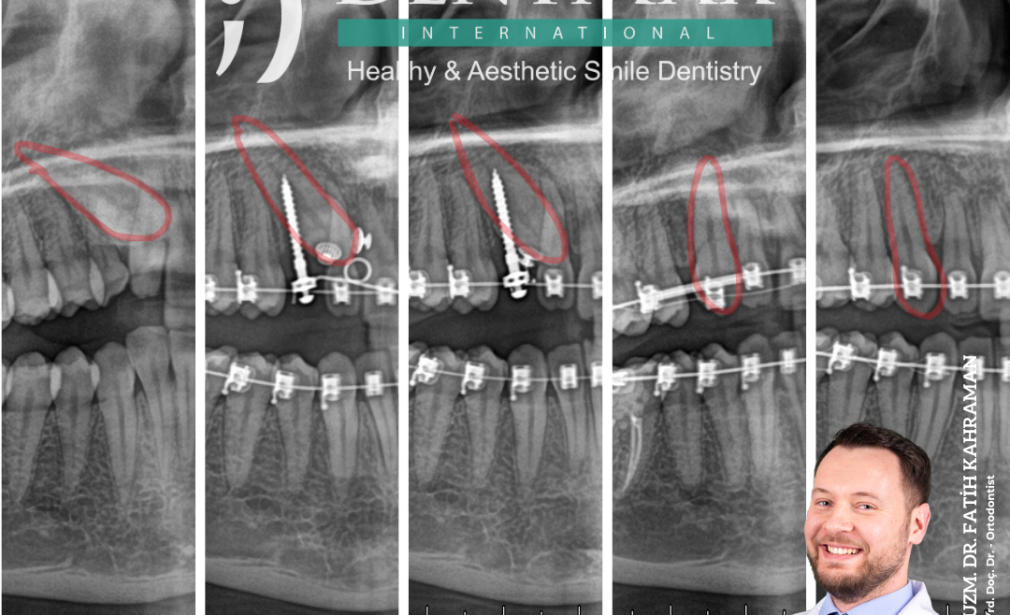

Gömük dişlerin ortodontik tedavisi, hastaya özel planlanan bir süreçtir. Bu tedavi genellikle röntgen ve dijital görüntüleme teknikleriyle başlar. Dişin konumu ve çevresindeki dokuların durumu incelendikten sonra, cerrahi bir müdahale ile dişin üzeri açılarak ortodontik aparatlarla doğru pozisyona sürdürülmesi sağlanır.

Ortodonti Uzmanı, gömük köpek dişlerinin tespiti için periapikal röntgen, panaromik röntgen veya konik ışınlı bilgisayarlı tomografi röntgenlerini inceleyip değerlendirir. Ortodontistler rahatlıkla erken dönemde teşhis koyabilecek bilgi ve donanıma sahiptiler. Erken teşhis her branşta olduğu gibi ortodontide de oldukça önemlidir. Çocuklardaki ilk ortodontik muayenenin, üyesi olduğum Amerikan Ortodonti Derneği’nce 6 ila 7 yaşları arasında 8 yaşına girmeden muhakkak yapılması öneriliyor.

- Konum tespiti: Röntgen ile gömük diş tespiti uygulaması sürecinin genel adı.

- Damaktaki gömülü köpek dişinin sürdürülmesini başlatma ameliyatı: Kliniğimizde dişin çevresindeki yumuşak ve sert dokuyu tamamen anestezi altında hiç ağrınız kaldırıp dişe fiziki olarak ulaşıyoruz. Ulaştığımız gömük dişi klinik tabloya ve planlamaya göre kapalı ya da açık diş sürdürme işlemiyle sürdürmeye. Başlıyoruz. Kısaca gömülü dişi, “kapalı sürdürme” işlemimizde ameliyat esnasında braketliyoruz. Ağız boşluğuna çıkarttımız tellerle dişlere çekme hareketi uyguluyor ve dişleri sürdürüyoruz. Ayrıca gömülü dişin sürdürülmesinde tercih ettiğimiz diğer yöntem olan “açık sürdürme” işlemimizde dişi braketlemeden, süreceği güzergahı düzenleyerek işlemimizi tamamlıyoruz.

- Gömülü dişin sürdürülmesi: Dişinizi doğal yollarla veya ortodontik kuvvetle sürdürüp ağız boşluğuna çekip, çıkartıyoruz. Ardından diş telleri ile dişlerinizi esas yerlerine getiriyoruz.